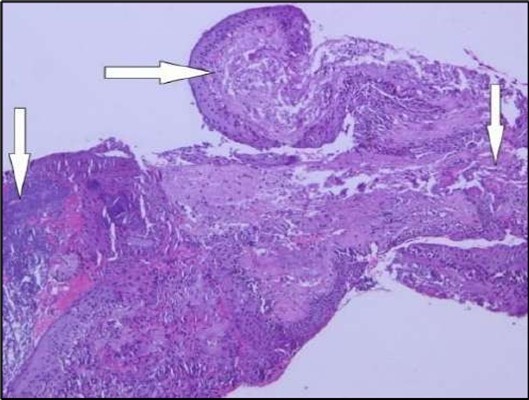

Two weeks post-surgery, the left eye showed significant healing, with a small conjunctival granuloma and vascularization at the ulcer margins. The cornea was clear with a central leading edge nasally, deep and quiet anterior chamber and clear lens. VA 6/6 bilaterally and IOP normal. Histopathology of excised conjunctiva showed non-keratinized squamous epithelium with superficial erosions, stromal elastosis, hemorrhage, and inflammatory infiltration, but no signs of granulomatous disease, malignancy, or viral evidence, findings consistent with idiopathic localized inflammatory process. The patient reported significant relief and satisfaction post-surgery, resuming normal activities. Treatment continued with oral prednisolone 25 milligrams every other day, tobramycin-dexamethasone ointment twice daily, and preservative-free artificial tears four times daily Figure 4, Figure 5a, Figure 5b, Figure 5c, Figure 5d.

Figure 5a.OS, Hematoxylin and eosin (H&E) stained section of the corneal specimen demonstrating full-thickness epithelial loss with underlying stromal necrosis.

Figure 5b.OS, High-power H&E view showing dense inflammatory infiltration within the corneal stroma composed predominantly of lymphocytes and numerous plasma cells (circles highlight plasma cells).

Histopathological examination revealed a dense infiltration of CD138-positive plasma cells within the excised conjunctival tissue (Figure 5b, Figure 5c, Figure 5d). This finding supports an antibody-mediated immunopathogenesis in Mooren’s ulcer, consistent with Type II and Type III hypersensitivity mechanisms described in the literature 20, 21. The prominent presence of CD138- positive plasma cells provide a clear pathological rationale for conjunctival resection, as excision of the immunologically active perilimbal conjunctiva effectively removes the local 'factory' of autoantibodies that drive corneal stromal destruction, thereby halting ongoing tissue damage 21.